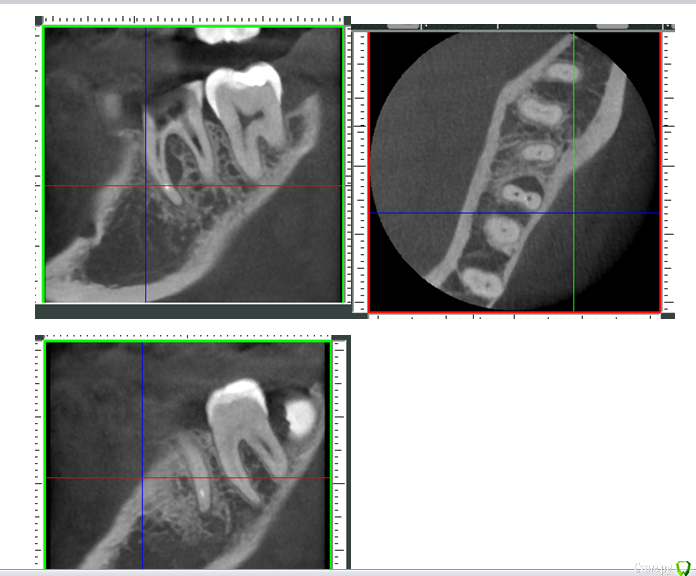

Mashelya Опубликовано 14 апреля, 2016 Поделиться Опубликовано 14 апреля, 2016 Всем добрый день! Пациентка 33 года. Пришла ко мне в ноябре 2015. Беременность 32 недели. Болит зуб 36. Снимок 1. Ноющая боль усиливается при накусывании. Перкуссия 36 положительная. Сделали снимок- штифт в дистальном канале. Расширение периодонтальной щели. Ну что делать- зуб болит, распломбировали, помыли почистили. Отделяемого не было. Два раза она ко мне приходила с интервалом 2недели. Мыли и каласепт. Договорились долечить после родов. Она больше не приходила, не звонила. Приходит ко мне дней 10 назад. Снимок 2. Говорит, за 2дня до этого скололась временная пломба, и, так как ко мне ехать далеко, а дома маленький ребенок, сходила в ближайшую стоматологию с целью поменять пломбу. Там ей естественно все вскрыли, снова чистили, мыли каналы. И вот теперь снова все болит. Ну в каналах, к слову, ничего не было(пасты имею в виду), ни на снимке, ни визуально. Снова все моем. Оставляю каласепт. Пациентка говорит, что прям вот уже все прошло, ничего не болит, уже жаждит вкладку и коронку. Я предлагаю сделать КЛКТ, так как в принципе вижу зуб в третий раз и то через полгода. И вот что видим. На медиальном корне большой воспалительный процесс. Дистальный тоже не в порядке. Перелечивание с вкладкой и коронкой примерно 25 т.р. Как считаете, это перспективно? Ведь процесс не на верхушке а между корнями, вот что меня смущает. Не хочу обнадежить человека, если потом все равно имплантация через пару лет. Ссылка на комментарий

Mashelya Опубликовано 15 апреля, 2016 Автор Поделиться Опубликовано 15 апреля, 2016 Обговорить все с пациенткой и лечить. Финансы это вопрос субъективный. Процесс у медиального корня виден на снимке до лечения. Каналы расширены были слабо, соответственно перфо или трещины там быть не должно. Широкая латераль, да. Так что мыть, мыть, мыть и паковать. Смотрите, это не может быть трещиной? Или как раз латераль? Ссылка на комментарий

DmitrySH Опубликовано 15 апреля, 2016 Поделиться Опубликовано 15 апреля, 2016 Больше похоже на анастомоз между каналами. 3 Ссылка на комментарий

Л Ю С Я Опубликовано 15 апреля, 2016 Поделиться Опубликовано 15 апреля, 2016 Отличное качество КЛКТ . +1 к анастомозу и латеральке. Пакуйте плотно, герметичная реставрация, через 6 мес ещё раз кт. Если пациентка не хочет и др причины, удаляйте. При правильном соблюдении протокола 80 % успеха. Если конечно от кор части что то осталось. Трещины обычно не так выглядят 1 Ссылка на комментарий

DmitrySH Опубликовано 15 апреля, 2016 Поделиться Опубликовано 15 апреля, 2016 Там если присмотреться, то возможно щелевидное подобие ММ канала. Но если в полости не удается зацепиться, то очень хорошо все мыть надо. Ссылка на комментарий